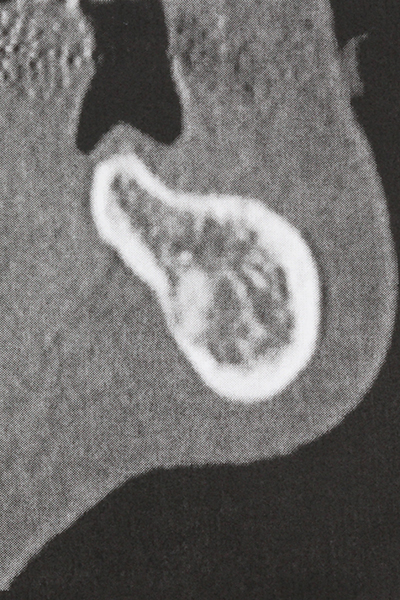

Piezo surgery has additional advantages when harvesting bone blocks. In addition to the high precision with osteotomy described above, the use of the thin saw tips specifically minimizes loss of material. Greater loss of material during harvesting can be expected with the thicker instrument tips, particularly when using Lindemann drills (Lakshmiganthan, Gokulanathan et al. 2012). The basal separation, which is necessary particularly for retromolar block transplants, is simplified by specially designed rectangular saws, with the result that piezo surgery is viewed as a precise, simple and safe procedure for harvesting retromolar bone blocks (Happe 2007) (Fig. 1-12).